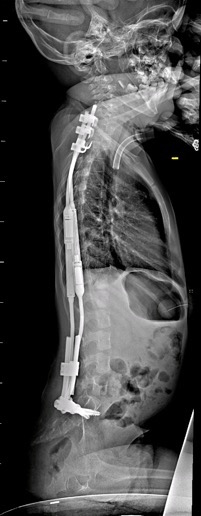

Seule solution pour soulager le petit garçon et freiner l’évolution de sa scoliose : l’implantation de vis dans son bassin et de crochets dans la partie supérieure de sa colonne vertébrale. Ces tiges en métal doivent suivre la croissance de l’enfant et ne bloquent pas les vertèbres qui peuvent encore grandir, a expliqué le CHU dans un communiqué.

Source : Radiographie de Louis, CHU d'Amiens-Picardie

« Leur pose à proximité des racines nerveuses reste très complexe et rare ; elles sont volumineuses au regard de la petite taille des os de l’enfant (vis de 7mm de diamètre à poser dans un couloir osseux de 8mm) », a ajouté l’établissement. L’utilisation du robot a permis aux chirurgiens de réduire le temps de l’intervention et la taille des incisions.